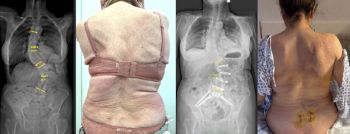

El equipo quirúrgico del Centro Médico Teknon, liderado por el Dr. Christian Morgenstern, director del Morgenstern Institute of Spine en Centro Médico Teknon, ha intervenido con éxito a una paciente de 80 años afectada por una escoliosis degenerativa dorsolumbar severa. El caso, que presentaba una curvatura de 57º en la zona lumbar y 42º en la dorsal, ha sido resuelto mediante la técnica ACR (corrección de columna anterior) en dos tiempos.

La intervención se dividió en dos tiempos quirúrgicos para maximizar la seguridad. En una primera fase, se realizaron abordajes mínimamente invasivos por vía anterior y lateral para rectificar parcialmente la columna, por lo que se logró reducir la curva lumbar de 56º a 39º de forma inmediata. Esta corrección previa permitió que la segunda fase, realizada por vía posterior, fuera mucho menos agresiva y pudiera ejecutarse de forma percutánea.